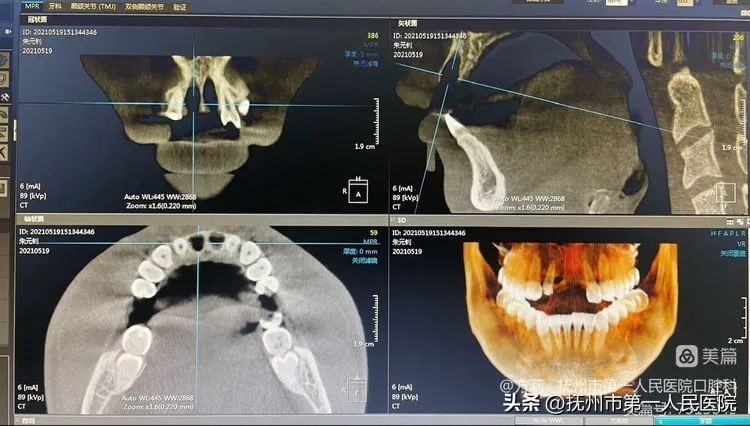

第二步:种植一期手术

2021年5月21日,于局部浸润麻醉下进行11、21即刻种植➕跳跃间隙植骨术!术后CBCT显示:唇侧骨量充足,植体位置良好!但因为植体初期稳定性不足,所以没有给患者进行即刻修复(术后即刻临时义齿戴入)!